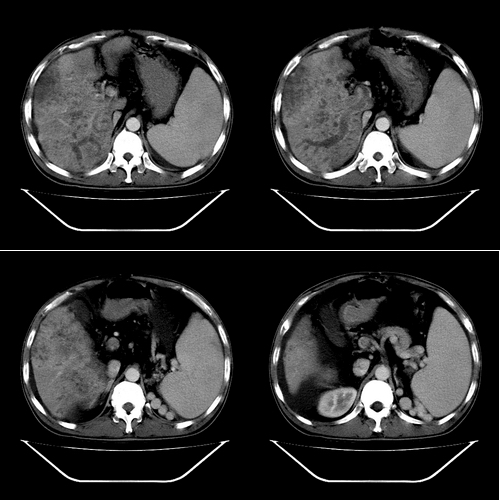

以下是引用yz在2006-6-2 12:20:00的发言:[br]肝左右叶比例失调,左叶体积明显缩小,肝边缘凹凸不平呈波浪状外观,肝左右叶可见不规则之斑片状低密度影,边界不清,以右叶为甚,肝门区增宽,增强后于动脉期病灶不均匀强化,门脉及延迟期均呈低密度,门脉主干及其右支无强化,以门脉右支明显,其内可见低密度影充填,门脉主干周围可见强化的细小侧支循环血管影。脾大,脾门血管明显增粗,脾后左侧膈脚前可见串珠状增粗强化血管影,并见胸腹水征。[br]1、考虑为弥漫性肝癌并肝门静脉主干及其右支癌栓形成,门脉海绵化。[br]2、肝硬化,脾大并门脉高压。[br]3、双侧少量胸水、腹水。